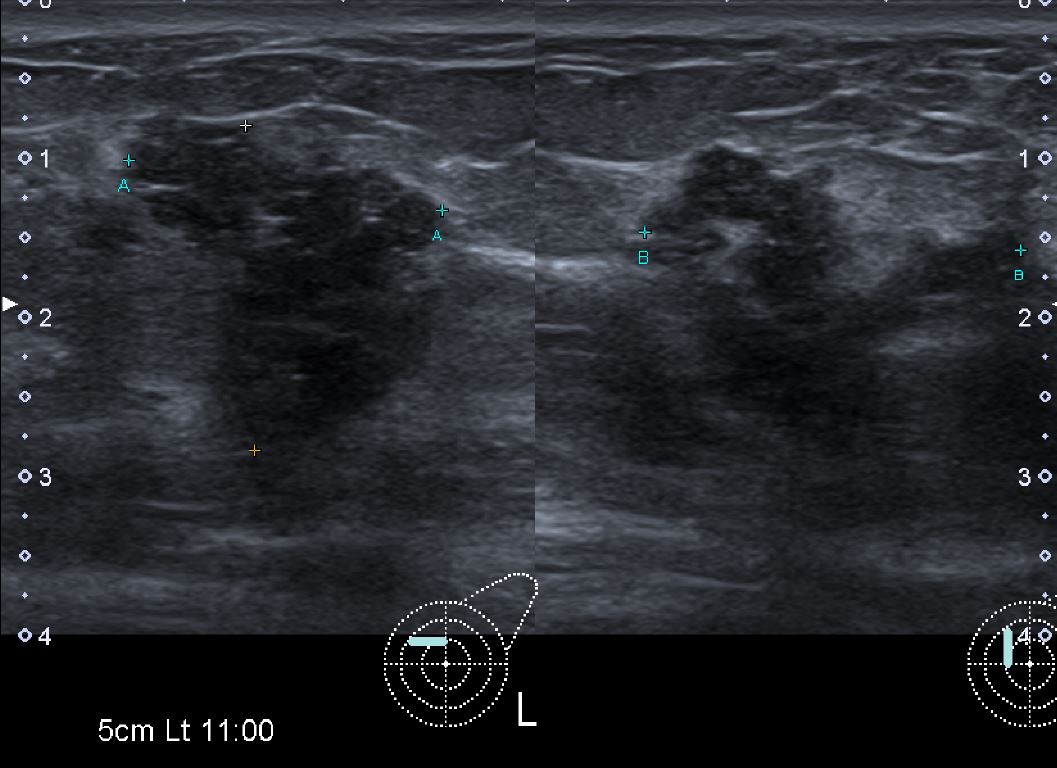

10  개월전부터 만져지는 멍울있어 내원하신 30대 여자분으로 초음파시행후

좌측유방 11시방향으로 조직검사시행후 상피내암진단되셨습니다.